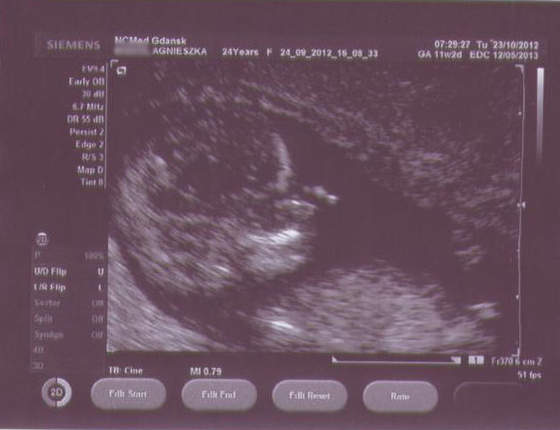

Pierwiosnek Pimpi Bimpi kręci się, wierci, nogami rozpycha i łapkami macha, pływa jak rybka, we wszystkich możliwych kierunkach, jednym słowem (właściwie dwoma) Dzidziul Wiercipięta. Chryste, w gardle mnie ścisnęło ze wzruszenia! Doktor mówi o nim per "Dzidziuś" (ZAWSZE!).

Dzidziulek zmierzony (4,76 cm). Tętno 160/min. Wg USG spodziewany termin porodu 7 maja, wg daty OM - 12 maja (trzeba zmienić datę, muszę napisać do Biedroneczki). Przezierność karkowa w porządku - 0,8 mm, nosek i wszystko co trzeba, też w porządku. Z TYM ŻE doktor powiedział, że COŚ TAM maleńkiego WIDAĆ między nogami (gdy zapytałam!), ale to o niczym nie świadczy, więc absolutnie nie możemy się tym sugerować (CHCĘ CÓRECZKĘĘĘĘĘĘĘĘĘĘĘ!!!). Aaaaaa, no i serduszko słyszałam - ale wypas!

A oto Pierwiosnek - dostałam 9 fotek, wybrałam dla Was 2 najbardziej widoczne